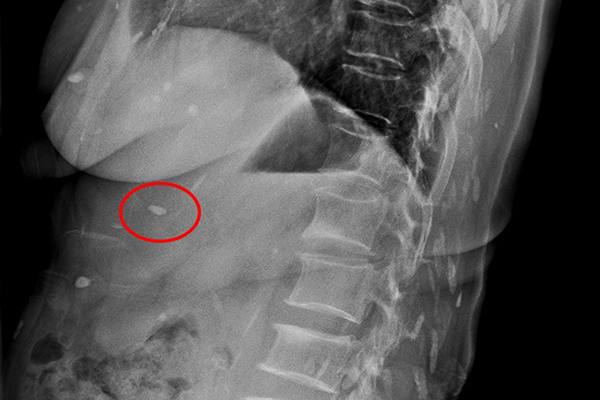

Hay ăn rau sống, sán lúc nhúc trong gan người đàn ông

Người đàn ông đến bệnh viện khám vì thường xuyên mệt mỏi, cơ thể suy nhược. Khi nội soi, bác sĩ phát hiện trong gan lúc nhúc sán.